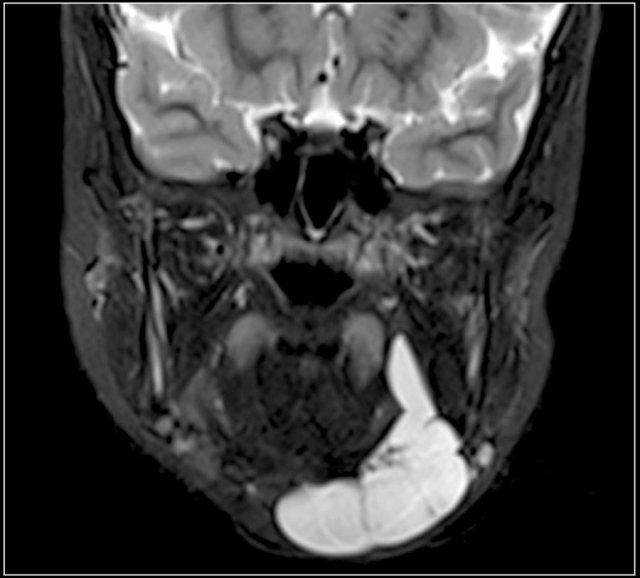

Đây là hình ảnh siêu âm của một u mạch bạch huyết điển hình.

MRI được thực hiện vì sự lan rộng của tổn thương chưa được xác định rõ ràng.

Here the T2-weighted image of the same patient.

Trên ảnh T1, nội dung bên trong có cường độ tín hiệu thay đổi, tùy thuộc vào hàm lượng protein hoặc máu.

Thường có cường độ tín hiệu cao trên ảnh T2.

T1 có tiêm thuốc tương phản có thể cho thấy sự ngấm thuốc của thành nang.